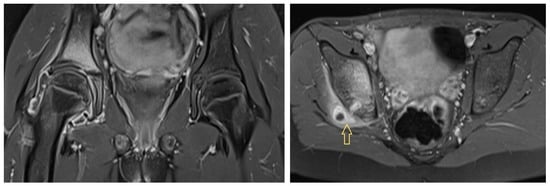

3.1.1. Patient 1

3.1.2. Patient 2

3.1.3. Patient 3

4.3. Diagnostic Imaging